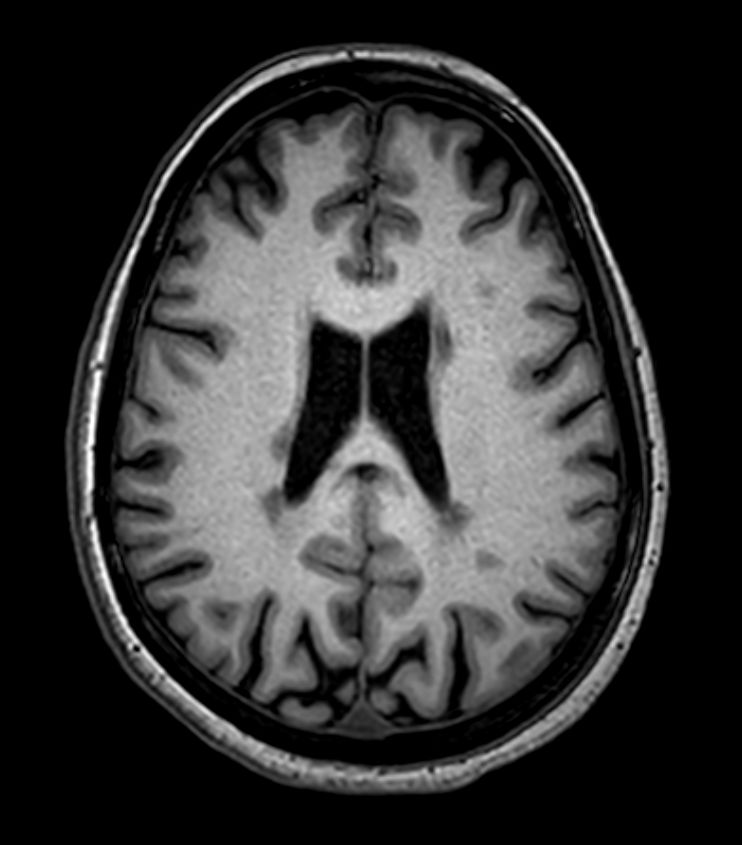

Multiple Sclerosis versus TIA

Standardized Multiple Slerosis MRI protocols typically require long scan times. Addition of Compressed SENSE enables faster exams, without compromise in image quality1. SWIp sequence has a high sensitivity to enhance contrast for deoxygenated (venous) blood or calcium deposits. This may help, when used in combination with other clinical information, in the diagnosis of various neurological pathologies. 3D (BrainVIEW) lets you acquire high resolution data in multiple directions in one scan. Isotropic voxel size enables reformats in any plane without loss of resolution.

3D T1w FFE Compressed SENSE

-

3D T1w FFE (reformat) Compressed SENSE